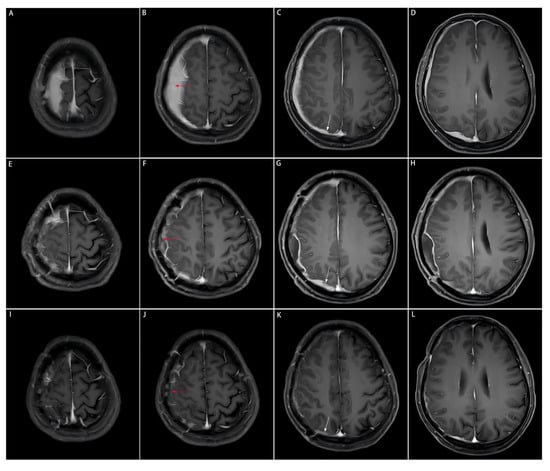

Figure 2.

Comparison of preoperative, postoperative, and post-medication enhanced-contrast MRI images. The area of the resected dural mass before and after the subtotal resection, and after medication on enhanced-contrast MRI images is indicated by the red arrow. The dural mass close to the cerebral falx on enhanced-contrast MRI images is indicated by the white arrow. This part is not surgically removed due to the tricky localization approach to the midline, but significantly shrinks after the three-month medication of prednisone acetate. (A–D): Enhanced-contrast MRI images preoperatively, (E–H): 2 months postoperatively, (I–L): 3 months of prednisone acetate.

The patient was postoperatively medicated with prednisone acetate (60 mg/d), calcium supplements and proton pump inhibitors to prevent complications. The follow-up imaging at 3 months postoperatively showed a significant reduction in diffuse meningeal thickening and enhancement, suggesting a sensitive response of IgG4-RHP to glucocorticoid therapy (Figure 2I–L).